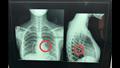

تمكن فريق جراحي بقسم جراحة القلب والصدر بمستشفى بنها الجامعي بمحافظة القليوبية، من إنقاذ حياة فتاة تبلغ من العمر حوالي 18 سنة، ابتلعت "دبوس" عن طريق الخطأ أثناء لبس للطرحة واستقر بالرئة، جرى عمل جراحة منظار شعب هوائية واستخراج الدبوس دون الحاجة لفتح صدر المريضة.

وكشف بيان لمستشفى بنها الجامعي، بقيادة الدكتور عمرو الدخاخني المدير التنفيذي للمستشفى، أنه جرى إجراء عملية طارئة لاستخراج دبوس طرحة من القصبة الهوائية اليسرى لفتاة تبلغ من العمر 18 عام، ابتلعته عن طريق الخطأ أثناء لبسها للطرحة ونزل في الرئة.

وأضاف البيان، أنه جرى على الفور إدخال الفتاة لقسم جراحة القلب والصدر، وجرى إجراء عملية منظار شعب هوائية صلب، وتم استخراج الدبوس دون الحاجة لفتح صدر المريضة